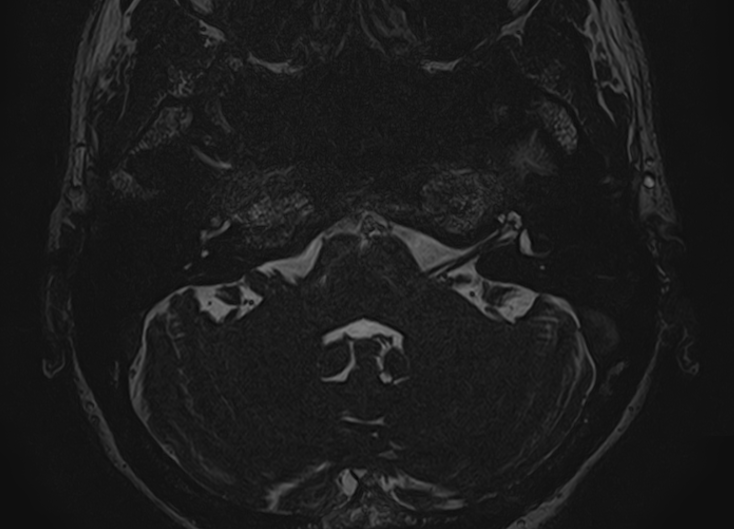

При подозрении на опухоль преддверно-улиткового нерва, образованиях лабиринта, воспалительный процесс МРТ внутреннего уха выполняется с внутривенным введением контрастного препарата.

Во время исследования пациент лежит на столе томографа неподвижно около 30 минут, на область исследования устанавливается специальная головная катушка для получения четких изображений.